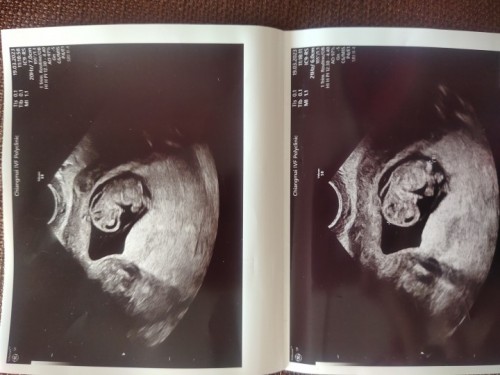

ความหนาต้นคอทารก

รบกวนช่วยดูภาพอัลตร้าซาวด์ให้หน่อยนะคะ กลัวมีภาวะต้นคอหนาเสี่ยงเป็นดาวน์ซินโดรมค่ะ อายุครรภ์ 9 w 2 d ยังไม่ได้ฝากครรภ์ค่ะ กังวลมากๆ เลยค่ะ

ตอนเราซาวด์ 9w ลักษณะน้องก็ประมาณนี้นะคะ อายุครรภ์มากขึ้นน้องก็จะเปลี่ยนรูปร่าง เข้า12weekคุณแม่ก็เจาะเลือดตรวจคัดกรองดาวน์เลยค่ะจะได้ทราบผลที่เเน่ชัด

หมอวัดขนาด NT แล้วยังคะ